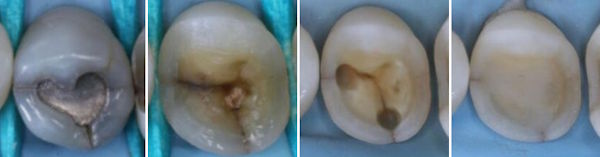

Die Biomimetik ahmt natürliche Verstärkungen von Oberflächen nach.

Hier werden die Höcker gekürzt, der Schmelz sandgestrahlt und mit Chlorhexidin desinfiziert, dann das Dentin mit Flow bedeckt, allenfalls auch Glasfasern quer über die Risse gelegt und einpolymerisiert. Dann Abdruck und Onlay.

Kritik aus mechanischer Sicht: Der distopalatinale Höcker wurde chronisch überlastet. Deshalb ist der Riss entstanden. Wenn auch auf das Onlay eine Querkraft einwirkt, kann ein Misserfolg entstehen.

Die Verstärkung des Zahnes mit einer Gold- oder Prozellankrone ist eine weitere Idee.

Durch eine Wurzelbehandlung werden die schlimmsten Zahnschmerzen und die Kaltempfindlichkeit eliminiert. Allerdings wird ein Zahn ohne Nerv etwas brüchiger. Zudem verursachen wurzelbehandelte Zähne manchmal auch eine Herdinfektion.